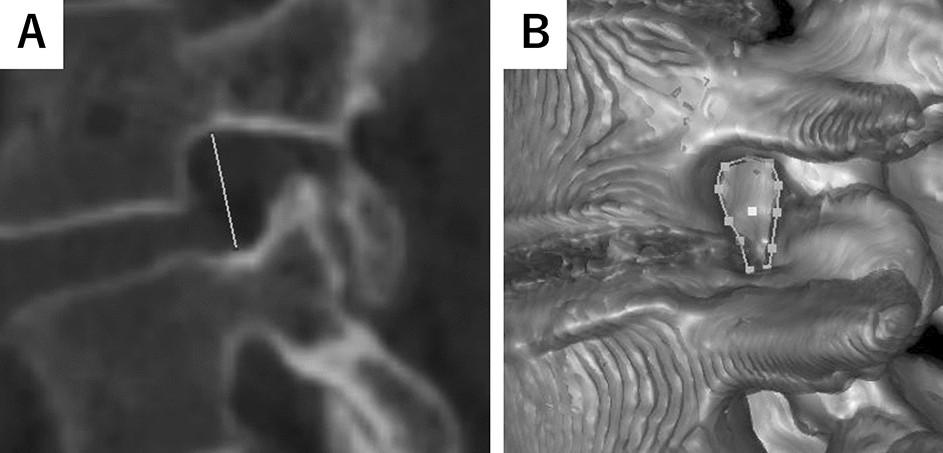

Figure 1

From: Gender differences in spinal mobility during postural changes: a detailed analysis using upright CT

Representative image of foraminal height and bone boundary area. (A) Representative Axial View of L4/L5 Foramen. The solid line shows the foraminal height (FH). FH is defined as the maximum distance between the lower edge of the superior pedicle and the upper edge of the inferior pedicle. (B) 3D Reconstruction of L4/L5 Foramen. Dotted circle indicates the bone boundary area (BBA) of the foramen. BBA is defined as the area enclosed by the posterior edge of the vertebral body, the lower edge of the superior pedicle, the anterior edge of the inferior articular process, the anterior edge of the superior articular process, and the upper edge of the inferior pedicle.